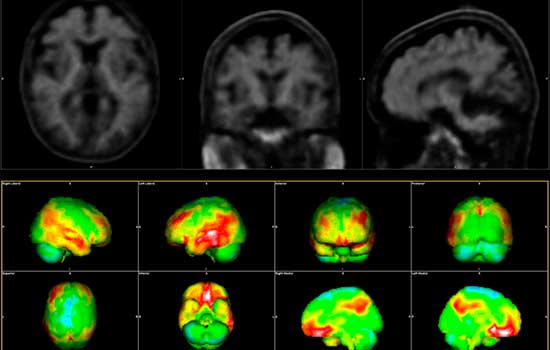

Como actor clave del ecosistema del Alzheimer, Siemens Healthineers impulsa el desarrollo y la validación de soluciones para todo el recorrido asistencial del paciente, desde el análisis de sangre para la detección precoz hasta técnicas de imagen avanzadas como la resonancia magnética (RM) y la tomografía por emisión de positrones (PET) para el diagnóstico y el seguimiento durante el tratamiento.

En el marco de ACCESS-AD, Siemens Healthineers facilitará la recogida de muestras simples de sangre en casa a los pacientes, lo que permitirá analizar biomarcadores clave del Alzheimer en las plataformas de laboratorio de la empresa, y trabajará también en reducir las barreras técnicas, operativas y económicas que limitan el acceso a técnicas de neuroimagen avanzadas en Europa, liderando el desarrollo y la implementación clínica de soluciones de RM y PET, escalables más allá de los centros altamente especializados.